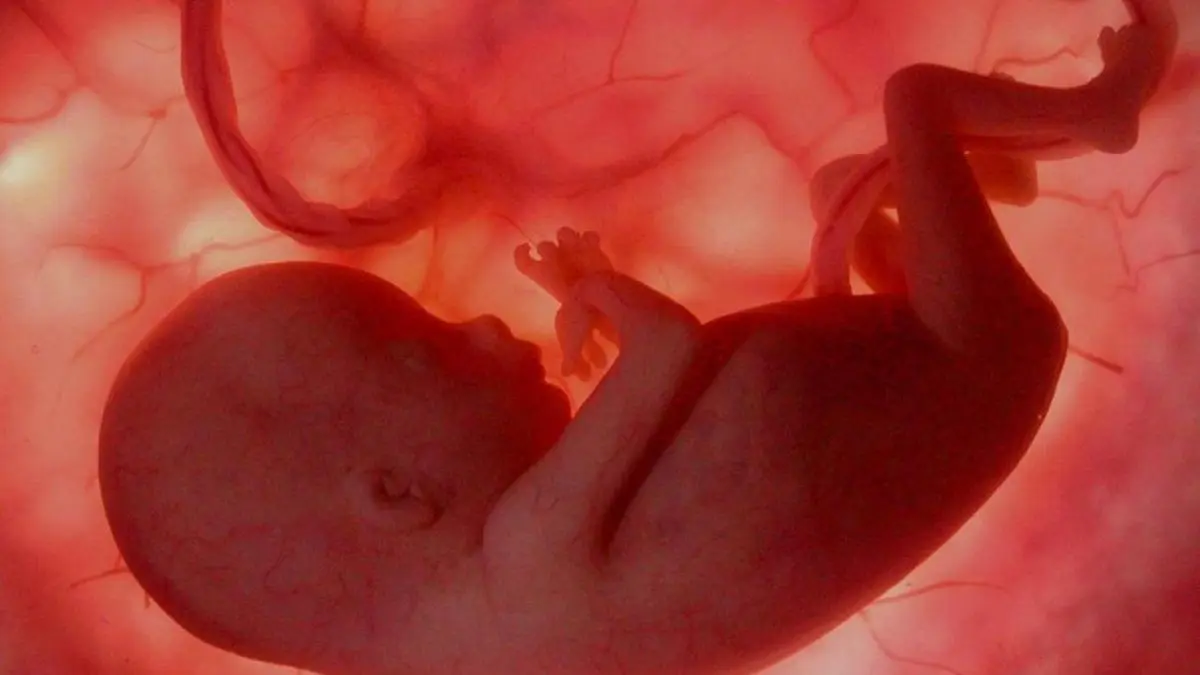

BARCELONA.- Un 85 % de los fetos se activan y reaccionan con gestos al escuchar himnos futbolísticos, según un estudio del Instituto Marquès, cuyos científicos han concluido que "la pasión por el fútbol empieza antes de nacer".

El 85 % de los fetos que han sido sometidos a la música de los himnos de diferentes clubes de fútbol se despiertan, mueven la boca y sacan la lengua cuando oyen esta música en el interior del vientre materno, aunque todos reaccionan de forma parecida independientemente del himno que estén escuchando.

El estudio ha concluido que el 85 % de los fetos se activan; el 60 % hacen movimientos de la boca y de la lengua y el 8 % reaccionan con una protrusión de la lengua.